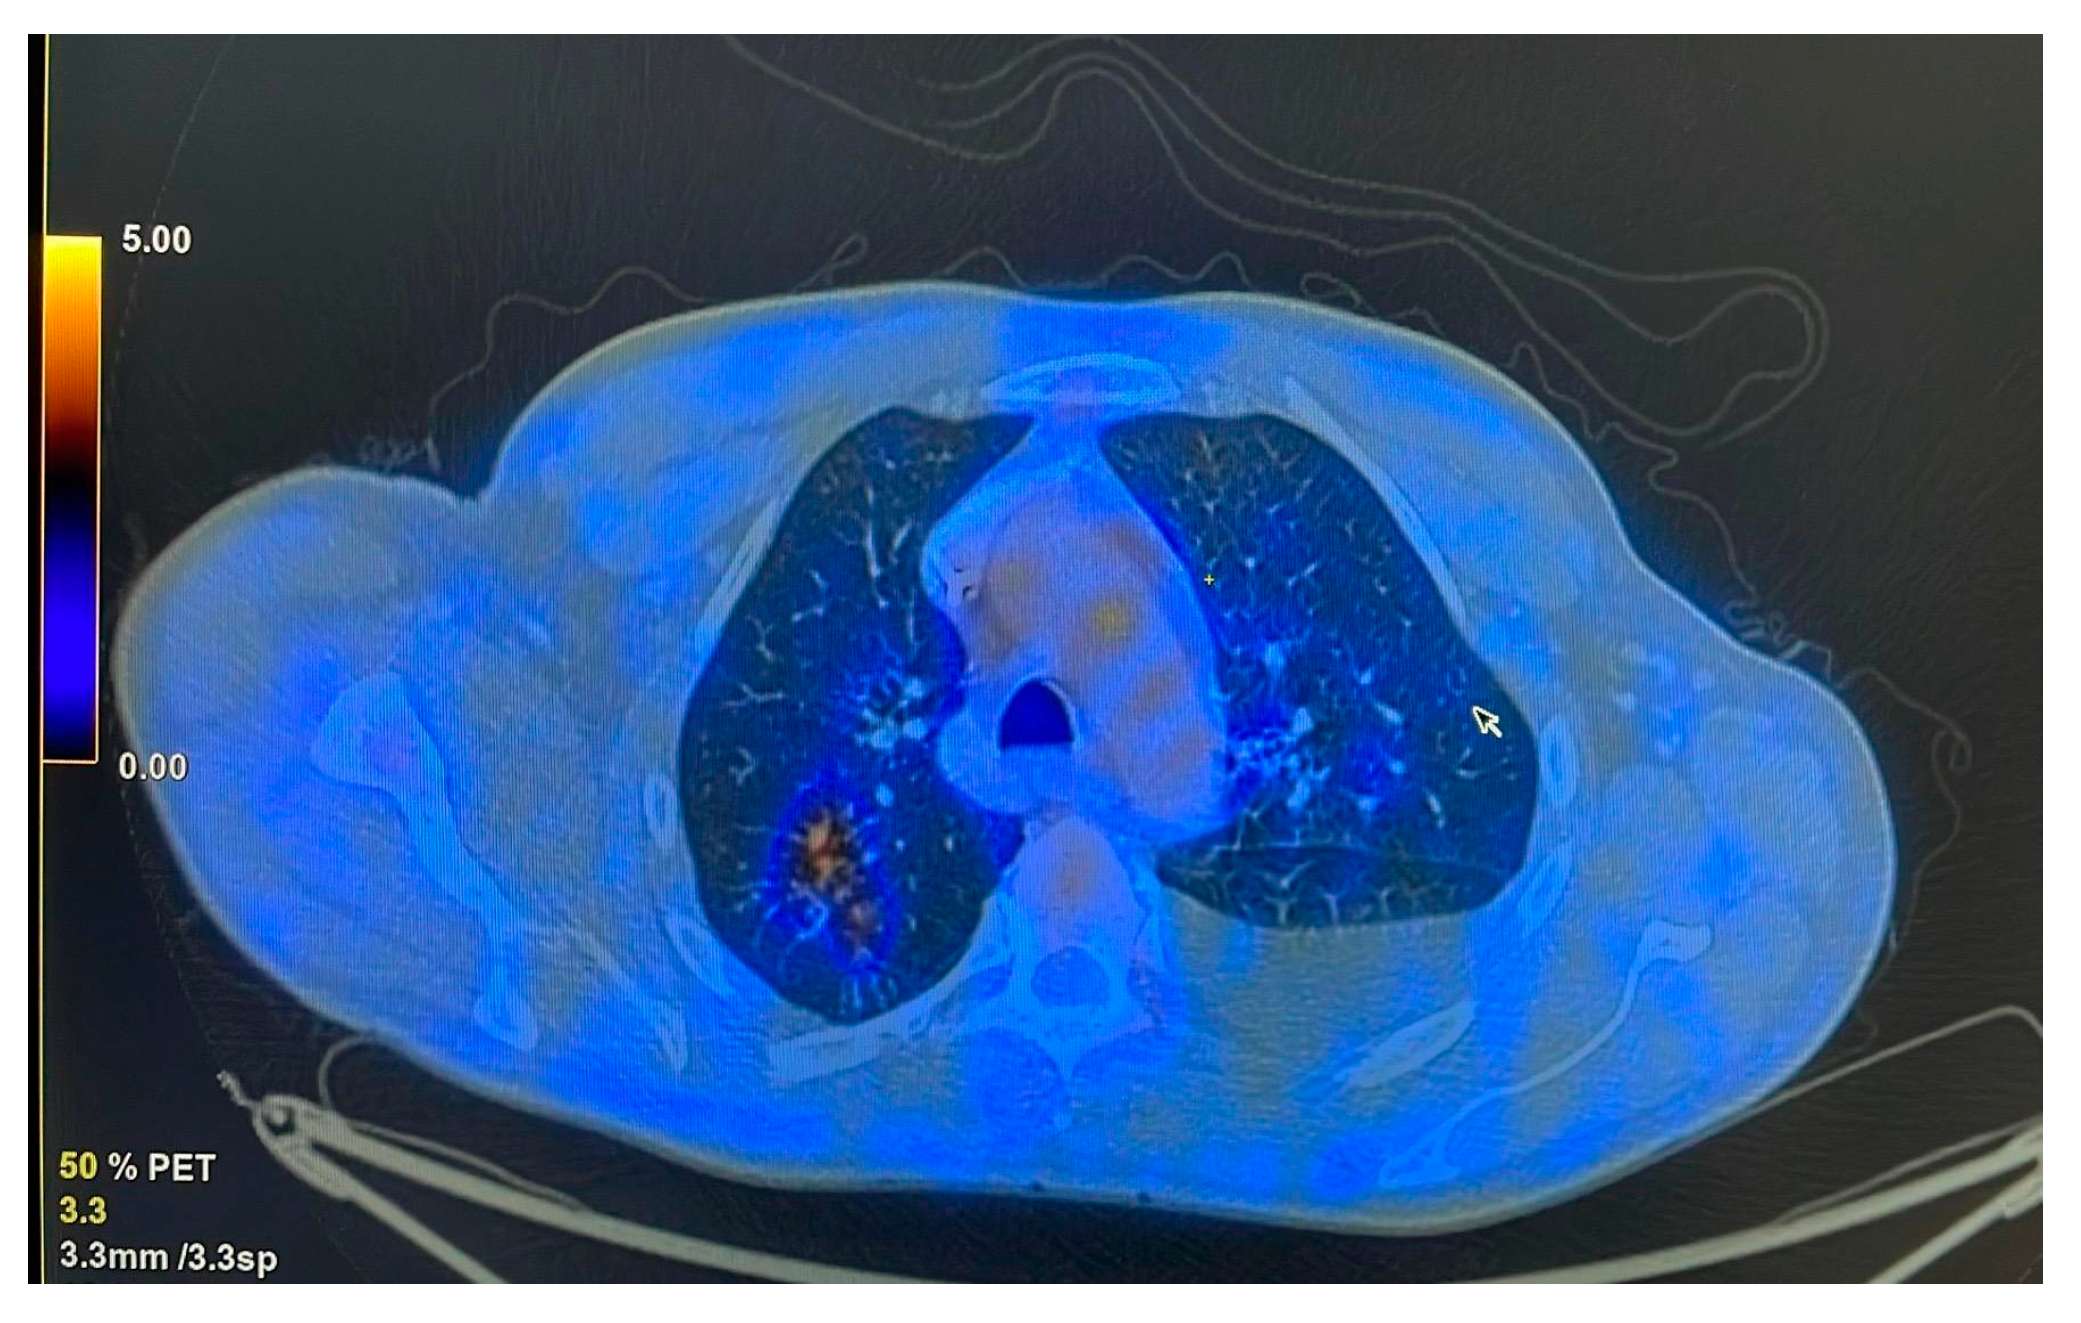

The CT scan performed at the initiation of treatment revealed micronodular “tree-in-bud” infiltration predominantly in the upper half (Figure 2), bilaterally, with left-sided pleural effusion and large-volume fluid in the abdominopelvic cavity.

Figure 2. “Tree-in-bud” infiltration in the posterior segment of the right upper lobe (RUL) before treatment.